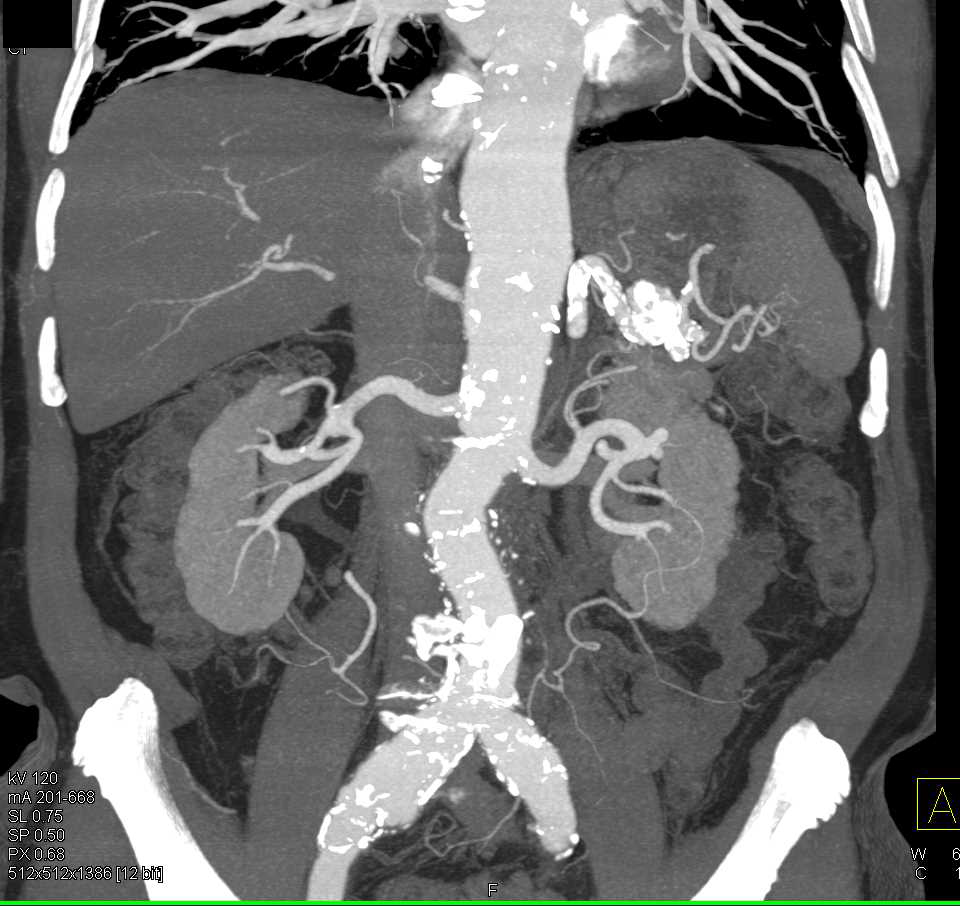

Carcinoid in the Root of the Mesentery Encases the SMA